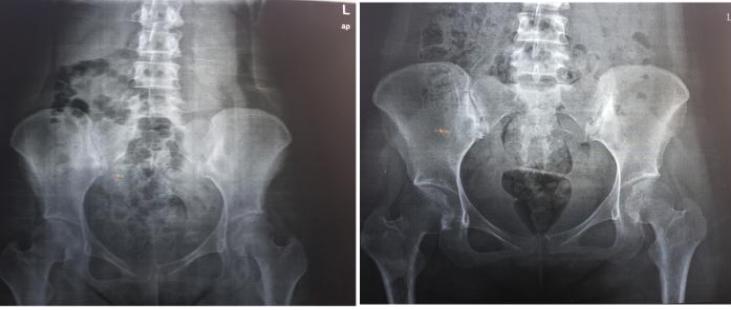

骨盆平片提示耻骨联合间隙6.4mm,中医科王浩医生检查发现,患者除了存在趾骨联合分离以外,还有致密性骨炎,而这才是引起她疼痛加剧的主要原因。

骨盆平片提示耻骨联合间隙6.4mm